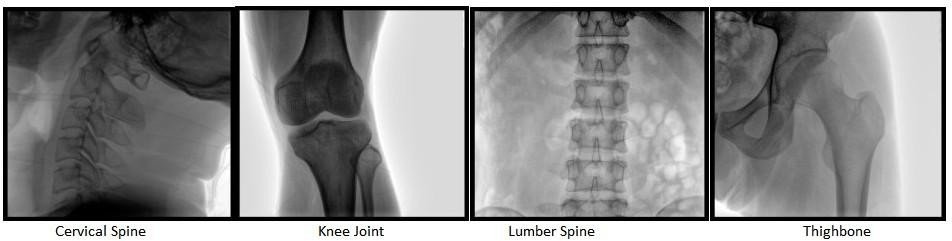

1. Basic Orthopedic C-arm - Image Intensifier & Flat Panel Detector

These types of C-arms typically have a power output of 3.5-5 kW and are equipped with image intensifier software (similar to a camera's CCD). Their cost is relatively low but can provide stable image output and meet basic orthopedic needs such as fracture reduction and intramedullary nail placement.

If your budget is more generous, you can choose the second-generation flat-panel C-arm, with increased the imaging field of view by approximately 30% compared to the image intensifier and resolved image distortion issues, truly from 'visibility' to 'clarity, coverage and confidence'.”